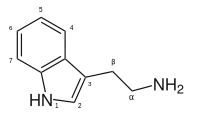

Substituted tryptamines, or serotonin analogues, are organic compounds which may be thought of as being derived from tryptamine itself. The molecular structures of all tryptamines contain an indole ring, joined to an amino (NH2) group via an ethyl (−CH2–CH2−) sidechain. In substituted tryptamines, the indole ring, sidechain, and/or amino group are modified by substituting another group for one of the hydrogen (H) atoms.